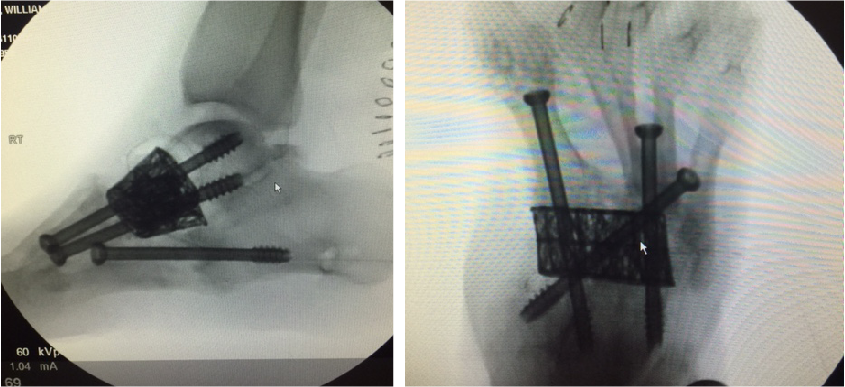

Additional emerging concepts with regard to beaming within our institution include the use of titanium trusses for cases involving significant midfoot bone loss. We have performed several of these reconstructions with good long-term limb salvage results. Structurally speaking, titanium trusses accept and resist the same loads as beams. A benefit of a truss is the bending stiffness and bending strength is a factor of 4 or above the structural mass required for the midfoot, which can easily resist failure.

In our experience, the mechanical forces of the midfoot in compression are enough to place the wedge without the need for fixation. However, we have routinely delivered beam screws through the titanium cage. We believe the truss acts as an additional load-bearing device with an independent section modulus that substitutes for the midfoot bone. When working in combination with a beam, we believe that the truss deflects forces from the beam.

Additionally, the titanium truss is filled with autogenous bone graft and orthobiologics, allowing for incorporation through the osteotomy site. This device allows for reconstruction in situations of excessive bone loss, acting as a replacement with the capacity for ingrowth. Follow-up demonstrates improved angular deformity correction with complete bridging on computed tomography (CT) scan.

Within these aforementioned confines, we believe the use of beam screws with titanium truss wedges can be an additional superconstruct that surgeons can add to their arsenal.